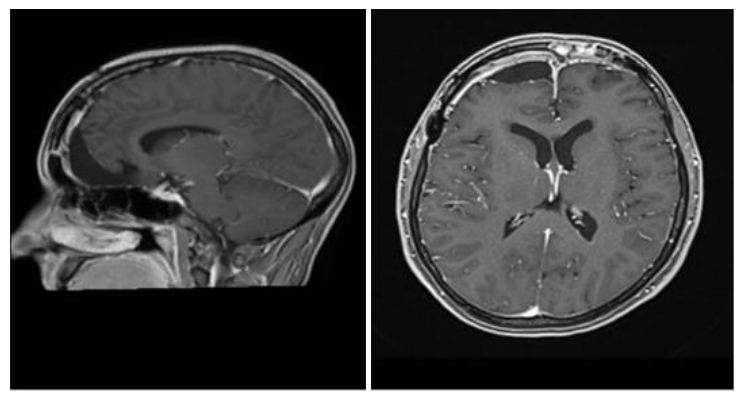

Due to these symptoms, a magnetic resonance imaging (MRI) scan of the brain was requested, which revealed a large extra-axial expansile mass with a broad dural attachment located on the floor of the anterior cranial fossa and involving the planum ethmoidale, crista galli, and olfactory groove. The mass showed a hypointense signal on both T1- and T2-weighted sequences, with intense and homogeneous enhancement after administration of gadolinium-based contrast agent. It measured approximately 5.8 × 5.0 × 4.9 cm in its largest diameters. There was compression of the anterior horns of the lateral ventricles, predominantly on the right side, in addition to a deviation of the midline structures toward the left by approximately 1.4 cm. The patient underwent a subsequent contrast-enhanced cranial MRI, which supported the diagnosis of a meningothelial lesion. Arterial and venous magnetic resonance angiography revealed a large left frontopolar vascular branch at the superior and medial margins of the lesion. Caliber asymmetry was observed between the transverse and sigmoid sinuses and cranial segments of the internal jugular veins, which were smaller on the left, probably representing hypoplasia on this side.